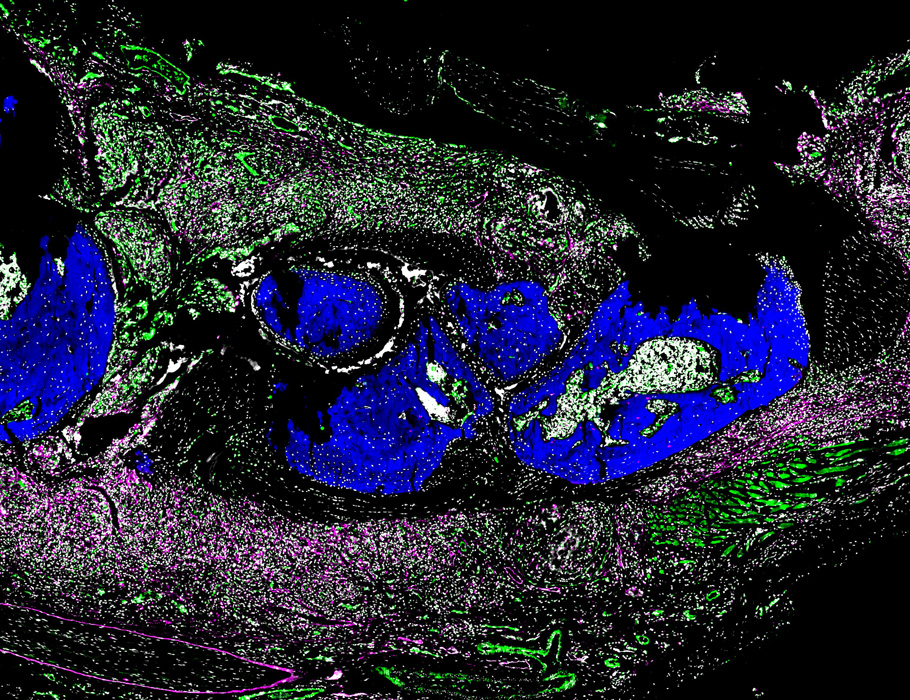

Research | Wünnemann et al. generate a subcellular resolution spatial map of the murine heart after myocardial infarction, revealing that immune cells can infiltrate the organ through the endocardium. doi.org/10.1038/s44161… rdcu.be/eKnDf

The latest from our lab in the cover of @CircRes: Macrophage-derived CCL24 exacerbates fibrosis and impairs cardiac function via CCR3. Work led by Preethy Parthiban in collaboration with Jop van Berlo's lab. Open access: ahajournals.org/doi/full/10.11…

Xavier_Revelo's tweet image. The latest from our lab in the cover of @CircRes: Macrophage-derived CCL24 exacerbates fibrosis and impairs cardiac function via CCR3. Work led by Preethy Parthiban in collaboration with Jop van Berlo's lab.